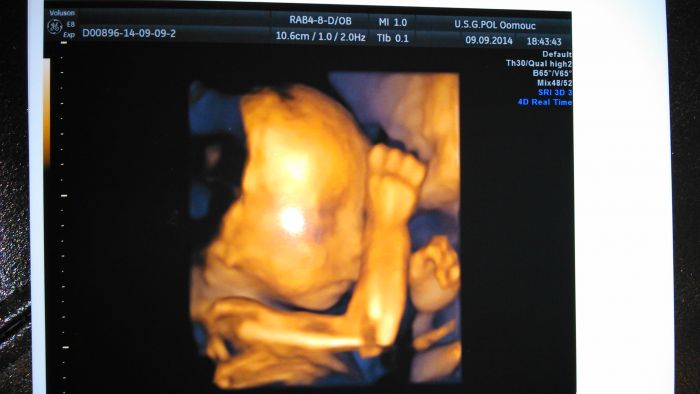

Tak jsme zpátky z 3D UTZ. Potvrdili nám tu holčičku,tak jsem ráda. :-) Je stejná jak naše Marunka. :-)

Ahoj holky ty diety jsou fakt mazec jak to tady píšete. Gábi gratuluju k chlapečkovi a tobě Brozanko k holčičce. Ostatním gratuluju k dobrým výsledkům na kontrolách. Holky máíte krásné fotečky z ultrazvuku.